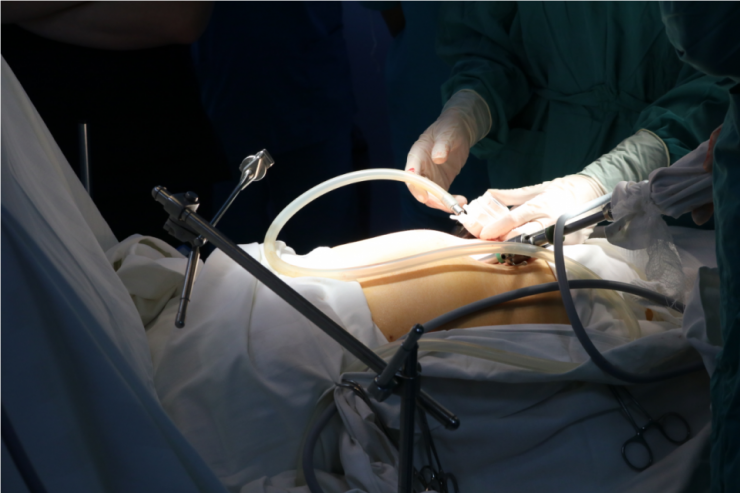

- В минувшем году в Совминке было открыто онкохирургическое отделение, в котором появилась возможность проведения процедуры - внутрибрюшной химиотерапии HIPEC. Сама процедура HIPEC впервые проводится в нашей стране на базе Совминки, так как профильных специалистов в мире считаное количество. Преимущественно процедуры проводятся во Франции, Израиле и других развитых странах. И положительная динамика результатов радует. Суть процедуры в том, что после удаления опухолей нагретый раствор химиотерапии вводится в брюшную полость, которая промывает и уничтожает оставшиеся раковые клетки. Таким образом эффективность лечения повышается и минимизируется воздействие химиотерапии на остальной организм.

Фото Совминки, операционная